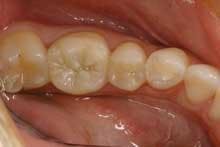

This patient is typical of our patients. She requested to have all the work in this quadrant completed at one time. The final result is a quadrant of posterior restorations that will last a long time and has improved the function and aesthetics of her teeth (Figure 2).

The benefit to the practice is important as well. We are able to work more efficiently on three or four teeth all at once than if we gave in to the "crown of the year" club mentality that we dentists help perpetuate in our patients. Also, we all know that the quality of the restorations is just a little bit better when they are all done at once - we don't "nick" the adjacent tooth while prepping; the laboratory technician has the ability to create correct and accurate proximal contacts and emergence angles; the lab technician also has the ability to help us correct or refine the patient's occlusion at this time.